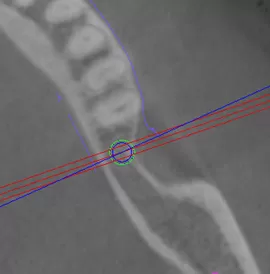

上記は左側が、ガイドを使用した場合の適切な位置、右側が、ガイドを使用しない場合に高確率で起こる不適な位置です。

本来入れるべき骨から逸脱している可能性があります。もちろん経験によってはここまで大きく外れることはありませんが、理論的には十分骨穿孔を起こす可能性があります。

上記は左側が適切にガイド使用した場合、右側がガイドをしない場合の比較です。